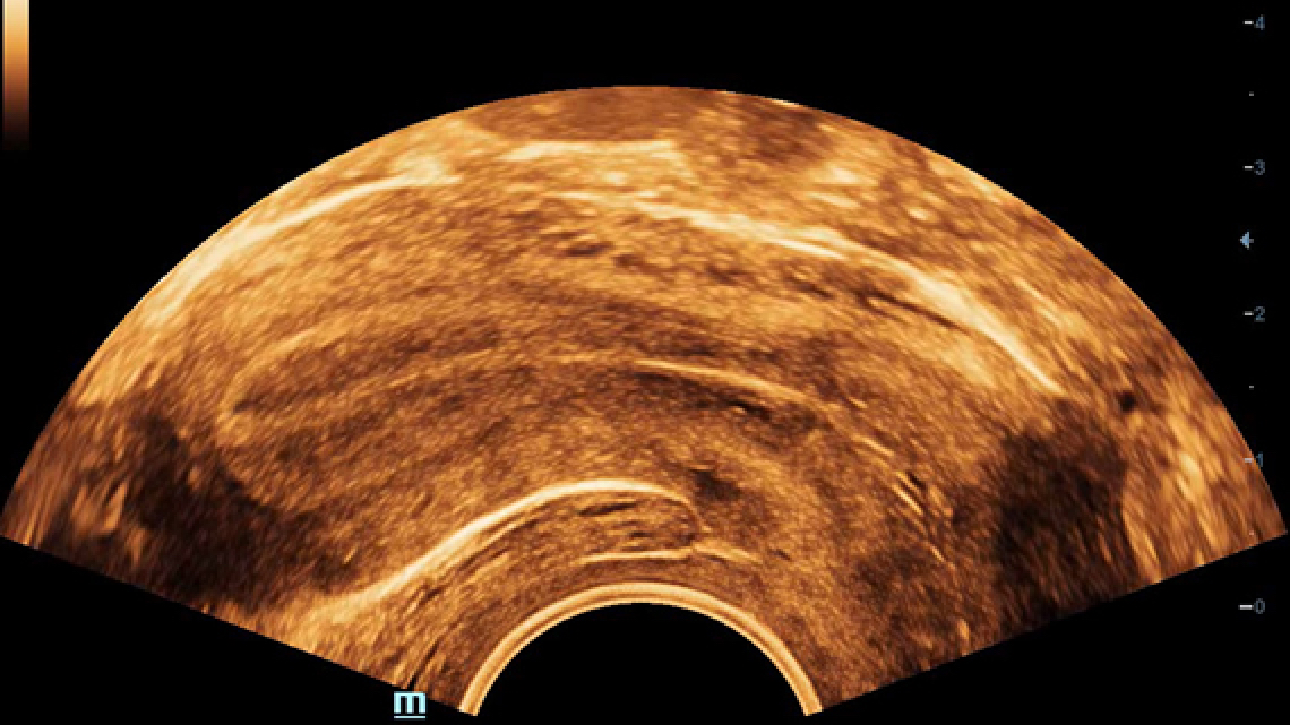

Imagens clĂnicas